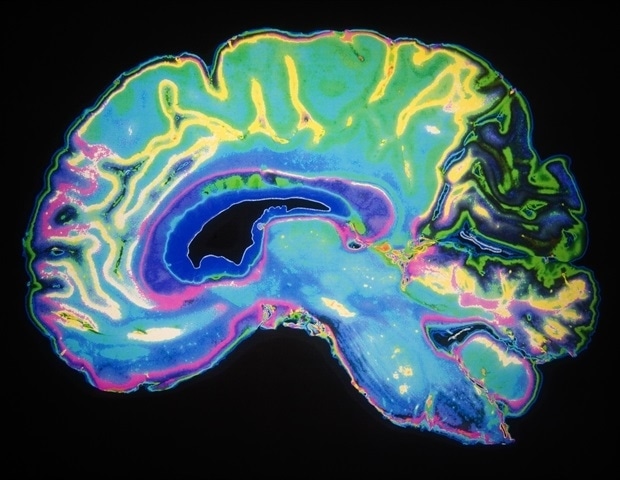

מחקר חדש שנערך על שחקני כדורגל בתיכון מצא כי זעזוע מוח משפיע על אות מוחי שלעתים קרובות מתעלמים ממנו אך

טיפול עתידי במחלת אלצהיימר עשוי לכלול תרסיס לאף. חוקרים מ-Università Cattolica ו-Fondazione Policlinico Universitario A. Gemelli IRCCS גילו שעל ידי